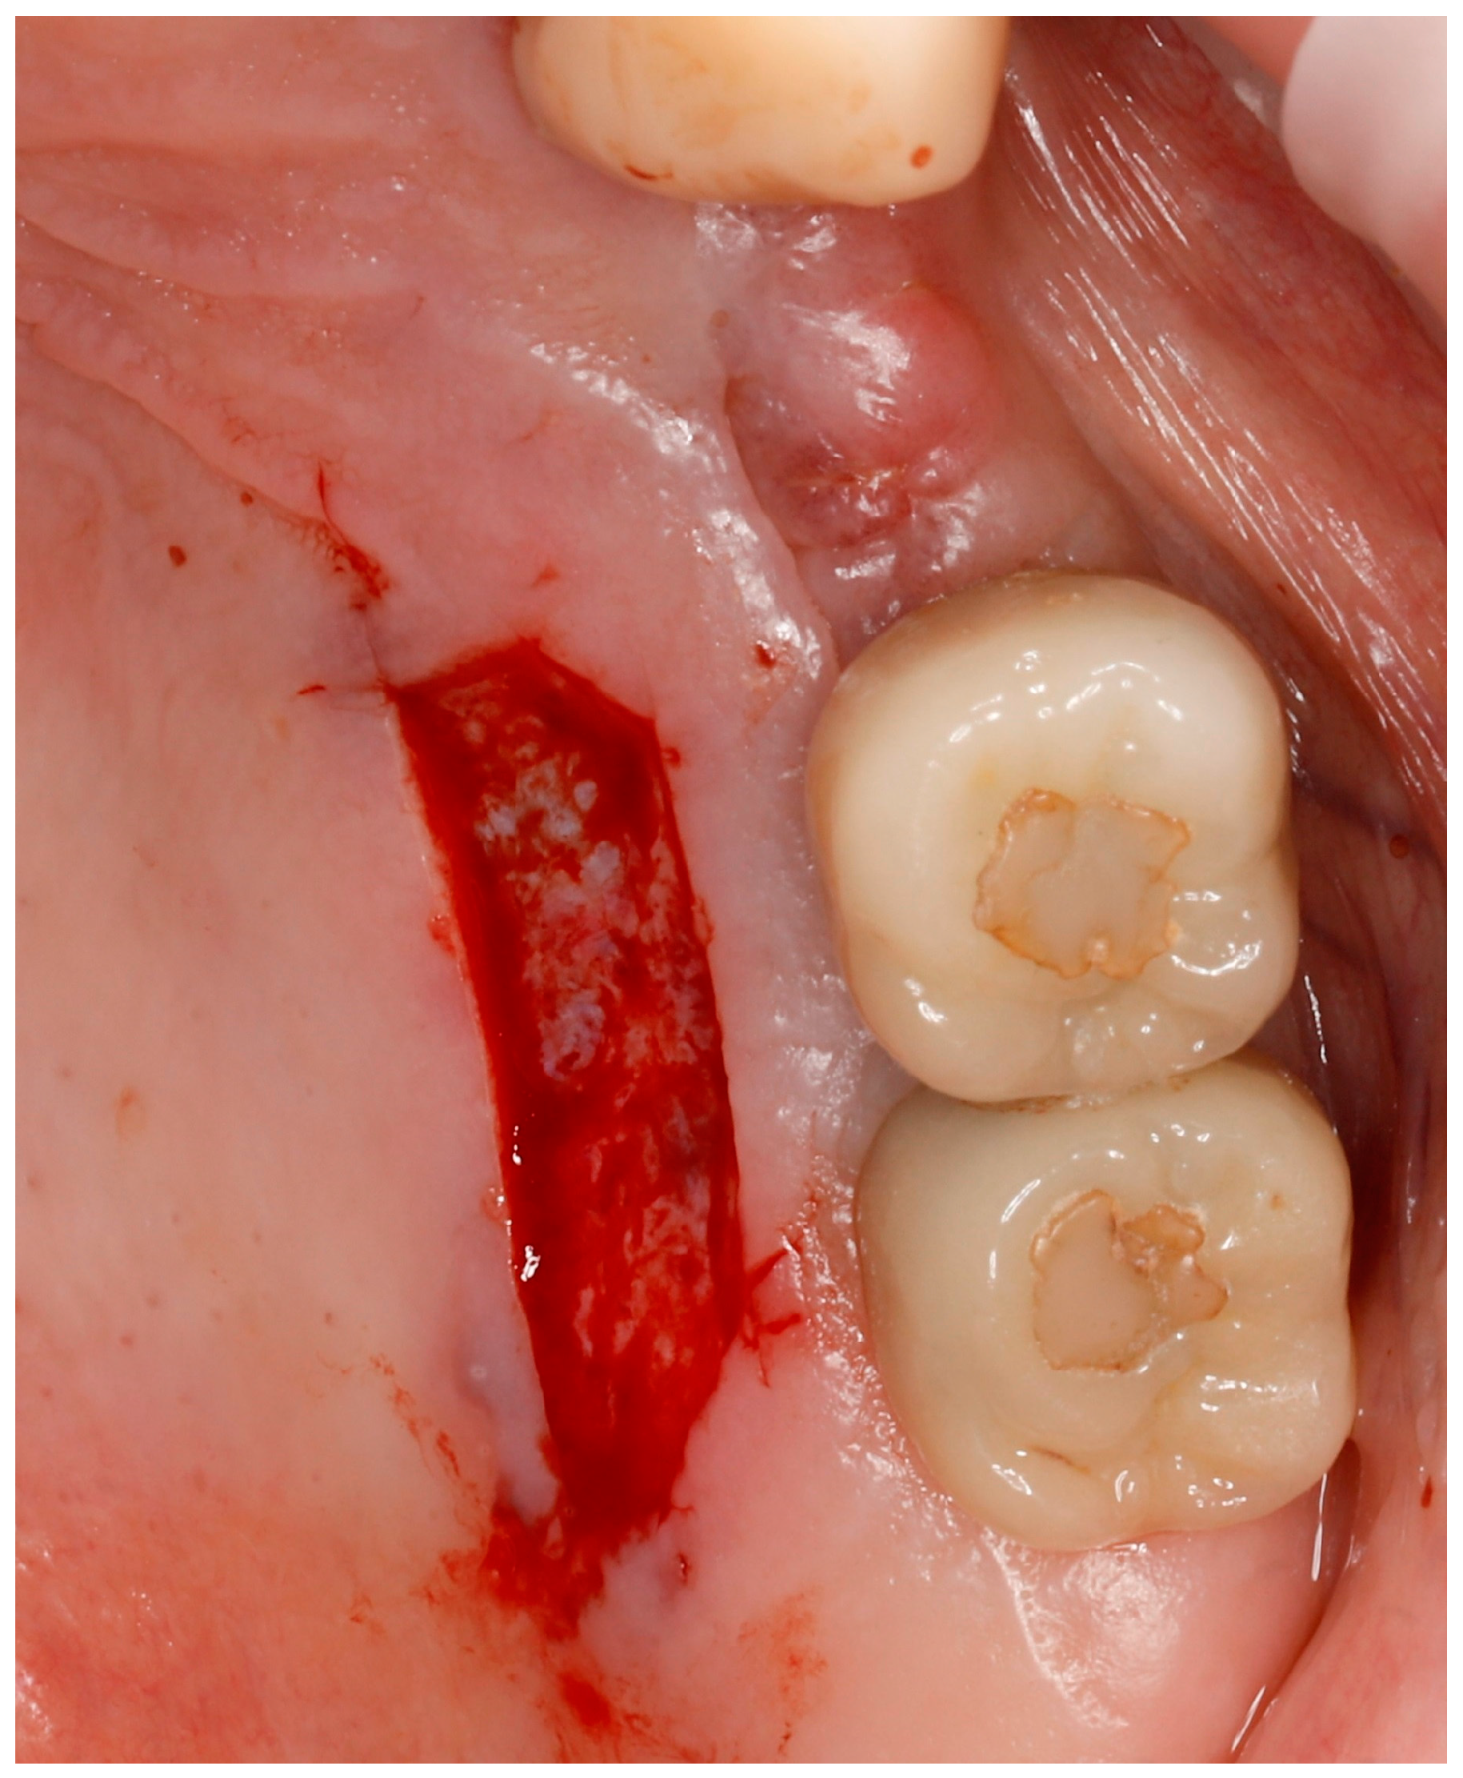

For almost sixty years, clinical periodontology has been defined by the use of autografts for two primary objectives: widening the keratinized mucosa and increasing soft tissue volume [5]. Autogenous graft-based approaches stand out as the most successful method for obtaining peri-implant soft tissue improvement [4]. A free gingival graft (FGG) is a common technique for rebuilding or expanding the keratinized mucosa area, while a connective tissue graft (CTG) serves to augment soft tissue volume, consequently promoting stability of interproximal marginal bone levels [3]. The majority of documented complications following FGG or CTG procedures are connected with the donor site [6] (Figure 1). Apart from a painful, open wound of the palate, the most common complications related to harvesting of FGG are as follows: excessive bleeding, postoperative bone exposure, and recurrent herpes lesions [7].

Figure 1. Photograph of a palatal wound created immediately after harvesting a free graft from the palate.